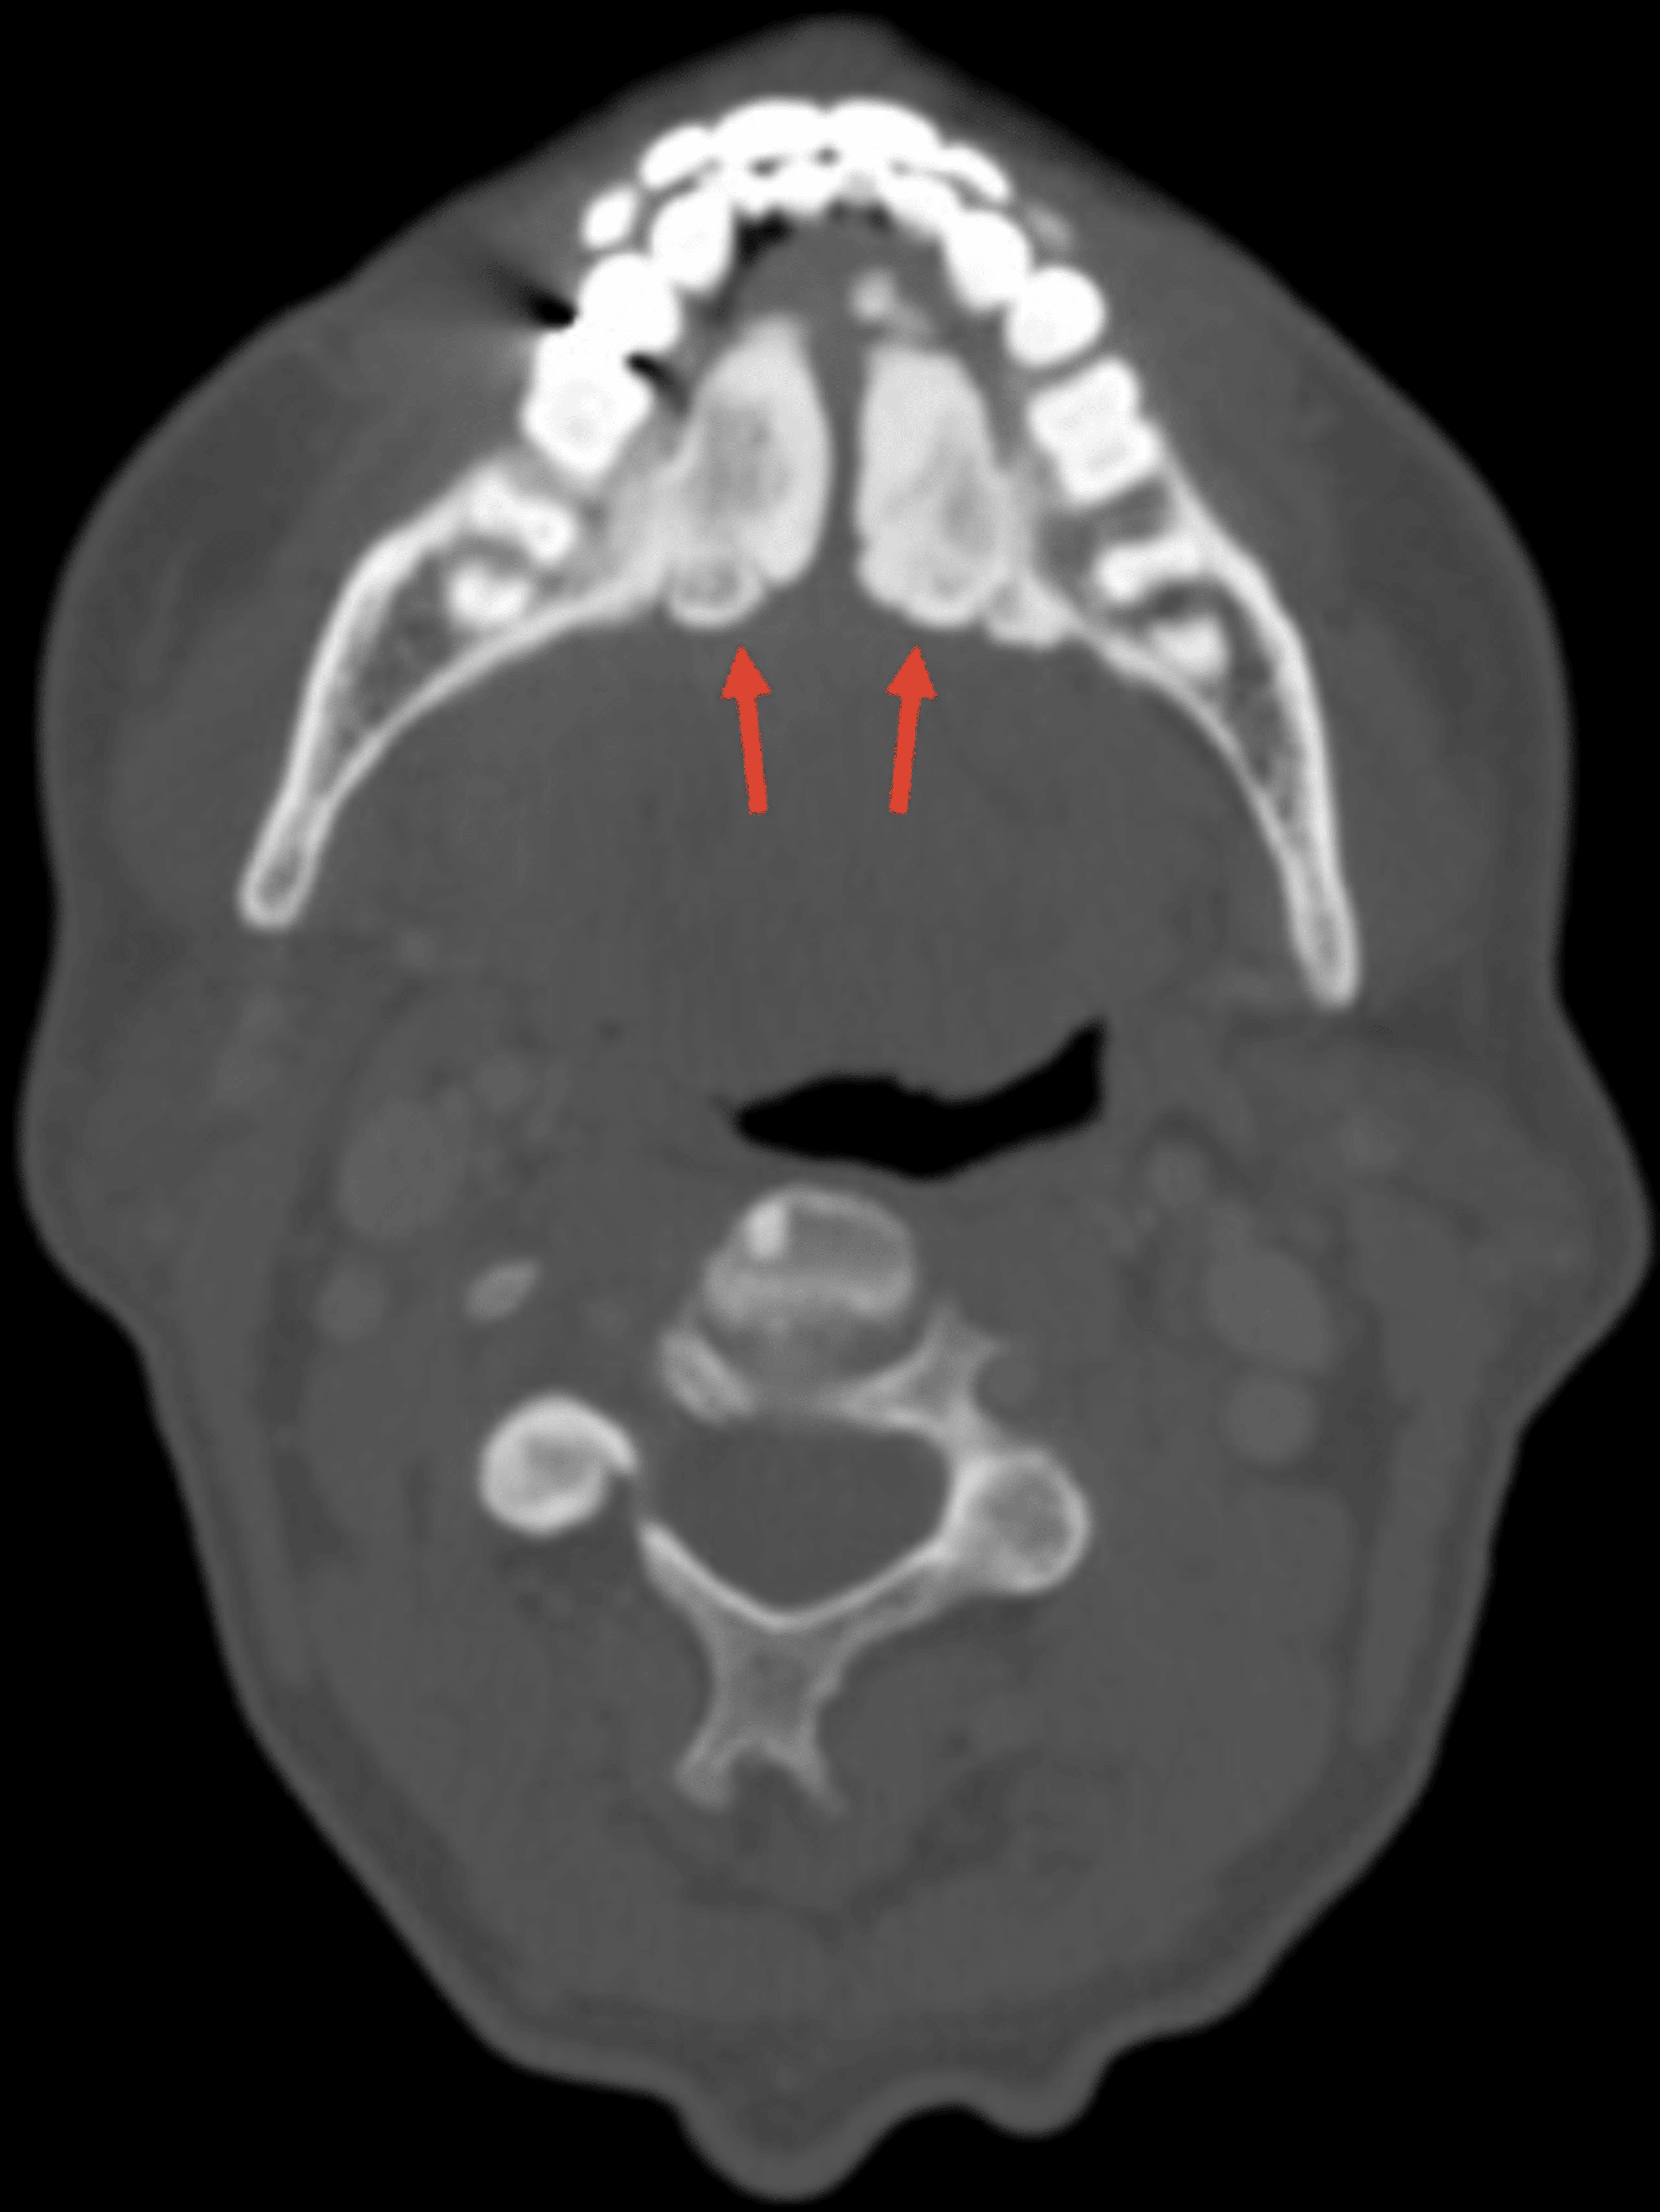

Sinusitis/Mastoiditis Undergraduate Diagnostic Imaging Fundamentals Flat Tymps Bilaterally There are three main types of tympanograms: Type a tympanograms look like a teepee, and indicate a normal middle ear system, free of fluid or physiological. Flat tymps also occur in stiff ear drums. Type b tympanograms feature a flat line with a normal ear canal volume. One reason for a flat tymp is a hole in the eardrum (perforation).. Flat Tymps Bilaterally.